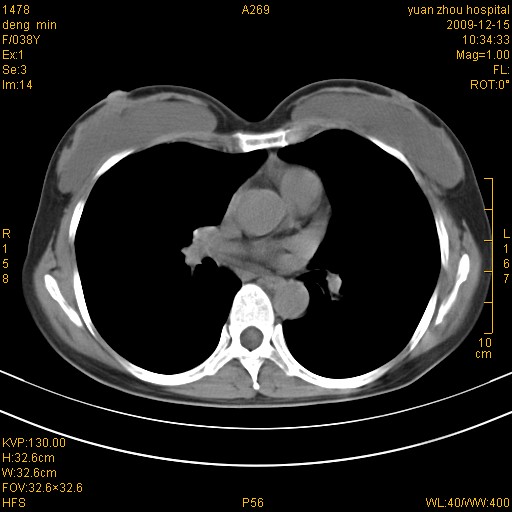

右肺中下叶、左肺上叶舌段及左肺下叶支气管扩张合并感染。